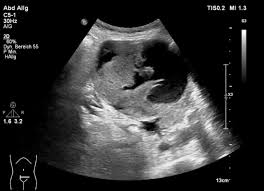

Die Ultraschalluntersuchung Sonografie ist meist die erste bildgebende Untersuchung bei Verdacht auf Blasenkrebs. Die Klassifikation Stadieneinteilung oder Staging genannt ist ein wichtiger Baustein für die Wahl der optimalen Therapie. Dabei kann der Arzt Blase Nieren und Harnwege begutachten.

Eine Ultraschalluntersuchung ermöglicht auch Blasensteine oder einen Blasentumor zu entdecken. Wirken Lymphknoten verdächtig veranlassen Ärzte in der Regel eine Biopsie oder Lymphknotenentnahme. Per Ultraschall lassen sich auch mögliche andere Ursachen für Beschwerden erkennen beispielsweise Nieren- Blasen-. Blasenkrebs kann als Folge einer Strahlentherapie entstehen. Blasenkrebs Mit der Diagnose Blasenkrebs hat der Patient nicht gerechnet. Sofern der Verdacht auf Blasenkrebs besteht nimmt der Arzt eine gründliche Untersuchung vor. Sie stellt zusammen mit der Biopsie Gewebeprobeentnahme die wichtigste Untersuchung für die Diagnose von Blasenkrebs dar. Ziel der Diagnostik ist eine möglichst frühzeitige Diagnosestellung und die Erhärtung oder Ausräumung des Verdachts auf Blasenkrebs. So stellen Ärzte beispielsweise bei Patienten mit einem Gebärmuttertumor ein erhöhtes Risiko für.

Die wichtigste Untersuchung zur Diagnose-Stellung ist die Spiegelung der Harnblase die sogenannte Zystoskopie. Es gibt keine Tumormarker im Blut die spezifisch für Blasenkrebs sind. Per Tastuntersuchung nimmt er dabei die Nierengegend den Unterbauch und die Geschlechtsorgane unter die Lupe. Blasenkrebs Mit der Diagnose Blasenkrebs hat der Patient nicht gerechnet. Liegt ein invasiver Harnblasentumor vor sind tiefgreifende Maßnahmen nötig. Wirken Lymphknoten verdächtig veranlassen Ärzte in der Regel eine Biopsie oder Lymphknotenentnahme. Die Ultraschalluntersuchung Sonografie ist meist die erste bildgebende Untersuchung bei Verdacht auf Blasenkrebs.